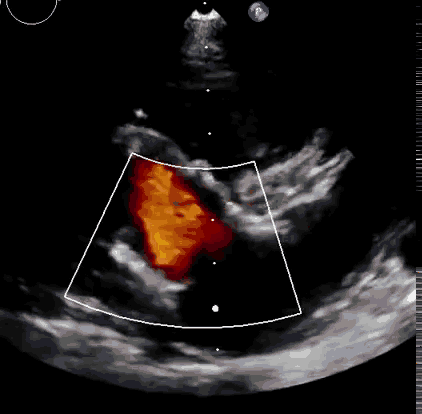

2021年11月14日星期日,復(fù)旦大學(xué)附屬中山醫(yī)院(以下簡稱中山醫(yī)院)葛均波院士團隊成功應(yīng)用經(jīng)血管介入三尖瓣置換產(chǎn)品Lux-Valve Plus完成臨床前研究,并獲得圓滿成功!此次研究的成功預(yù)示經(jīng)血管三尖瓣產(chǎn)品Lux-Valve Plus已完成臨床前準備,即將開啟后期的正式臨床研究!

上海中山醫(yī)院葛均波院士、錢菊英院長、周達新教授、潘文志教授、潘翠珍教授、李偉教授共同完成此次臨床前研究。術(shù)后葛均波院士對Lux-Valve Plus的器械操作性能給予了高度評價,DSA和超聲影像也顯示出在本次研究中Lux-Valve Plus的安全性和有效性俱佳。

本次臨床前研究經(jīng)右側(cè)頸靜脈置入LuX-Valve Plus輸送系統(tǒng)可調(diào)彎鞘管,在DSA及超聲引導(dǎo)下將人工三尖瓣瓣膜植入到原有三尖瓣位置,利用獨特的錨定技術(shù)將人工瓣膜支架可靠固定在預(yù)定的位置。

Lux-Valve是全球第一款具有我國完全自主知識產(chǎn)權(quán)的經(jīng)導(dǎo)管介入三尖瓣置換系統(tǒng),利用前瓣夾持及室間隔錨定的復(fù)合方式進行瓣膜裝置的固定,不依賴瓣環(huán)徑向支撐力,同時采用自適應(yīng)復(fù)合裙邊材料,有效的貼合密封柔軟的三尖瓣瓣環(huán),針對于三尖瓣返流的患者有優(yōu)異的療效。Lux-Valve Plus采用全新的經(jīng)血管輸送系統(tǒng),經(jīng)頸靜脈入路創(chuàng)傷更小,可以進一步降低手術(shù)風(fēng)險。相信在后期正式臨床研究開展中,Lux-Valve Plus必定會為更多的三尖瓣反流患者帶來福音。